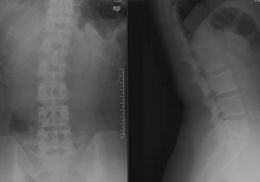

经典病例一

高* 女,腰痛伴左臀部疼痛麻木,左足麻木半月。

查体:腰5骶1棘间及左棘旁压痛、叩痛明显,疼痛向左臀部放射,左臀部外侧及左足底皮肤感觉减退,左跟腱反射减弱,左侧直腿抬高试验阳性(40°),加强试验阳性。

腰椎MRI示:L5S1椎间盘突出,左侧神经根受压。

(图)术前X线片